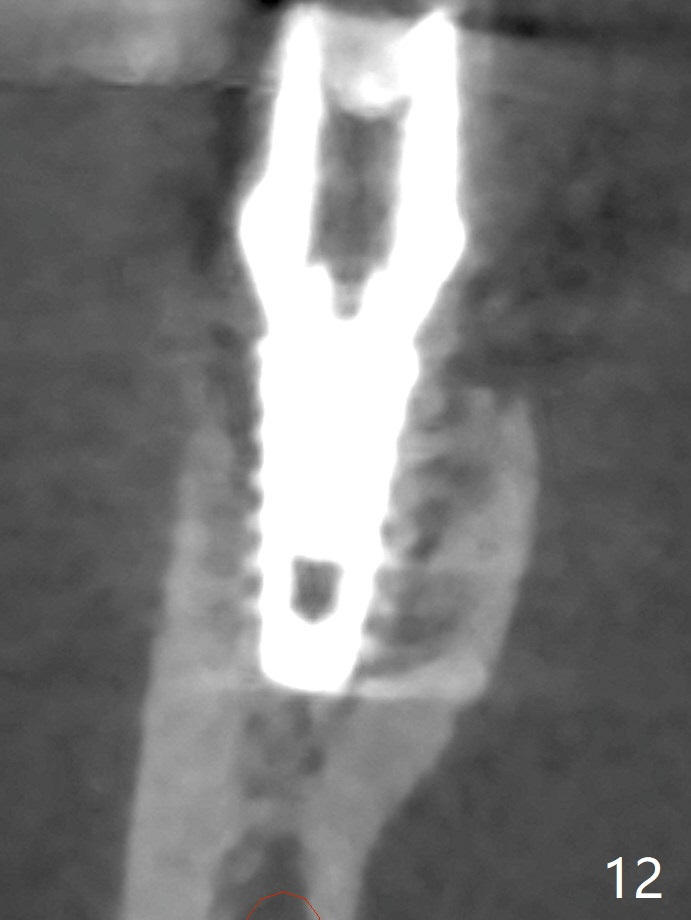

As planned, the crown of the tooth #30 with lingual (Fig.1 L) caries is removed and flattened with surgical handpiece so that the guide is able to be seated without interference. The osteotomy by 10.5 mm offset bone trimmer is lingual (Fig.2 white circle; due to in part the lingual caries and in part design error); in order to let the osteotomy to bounce back buccal, the part of the buccal roots are removed by surgical bur (arrows). The initial osteotomy by 2.2 mm drill is in the middle of the septum (Fig.3). After the last drill (3.5x11.5), the remaining roots are easily removed with proximators; a 4x11 mm dummy implant is placed with low stability and supracrestal lingual (Fig.4). Therefore a 4.5x9 mm final implant is placed with low torque. Following 4x11.5 mm drill, the torque increases to 20 Ncm. With insertion of healing screw, sticky bone (Fig.4 *: .5-1 mm cortical/cancellous allograft) is heavily packed around the implant (arrow), which apparently allows removal of the healing screw and placement of a 6x5.7(3) mm pair abutment without loosening the underlying implant. More bone graft is placed (Fig.6), followed by 2 pieces of PRF membranes. Although the implant is slightly buccally placed (Fig.7, due to over-removal of the buccal root, Fig.2 arrows), it is placed in the septum (Fig.8 S). To further compensate for the low implant stability, setting acrylic is applied in the edentulous area, particularly into the undercuts of the neighboring teeth (Fig.9 *) and around the abutment. The lingual margin of the acrylic dressing is extended (Fig.10 arrow) to cover the soft tissue defect associated with the lingual caries. As compared to the design (4x10 mm, Fig.11), the implant (4.5x9 mm, Fig.12) is placed buccal and ~ 2 mm deeper, reducing the chance of periimplantitis. The acrylic dressing is in place, but has mobility. The gingiva is healthy 2 weeks postop. The dressing is removed 1 month postop; the socket heals around the abutment buccal (Fig.13) and lingual (Fig.14). In spite of the immediate provisional, the abutment margin is substantially subgingival mesial 4 months postop, extremely difficult to take impression. A smaller diameter and longer cuff abutment is placed (Fig.15). The lingual gingiva heals normal 5 months postop, immediately before cementation (Fig.16).